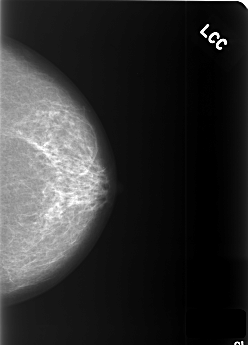

C_0412_1.LEFT_CC

LEFT_CC LINES 5512 PIXELS_PER_LINE 3960 BITS_PER_PIXEL 12 RESOLUTION 50 NON_OVERLAY